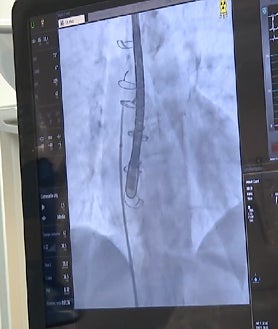

La intervención se realiza de forma mínimamente invasiva, accediendo al corazón a través de la ingle, lo que evita tener que abrir el pecho del paciente. Gracias a una técnica de imagen muy precisa llamada ecocardiografía transesofágica, los médicos pueden ver con detalle la zona de la válvula mitral y controlar con gran exactitud la colocación del dispositivo, aumentando así la seguridad y la eficacia del procedimiento.

El tratamiento consiste en introducir un catéter que coloca primero un anillo alrededor de la válvula mitral dañada, creando una base firme. Sobre ese anillo se implanta después una válvula biológica expansible que sustituye a la original y permite que la sangre vuelva a fluir correctamente por el corazón.